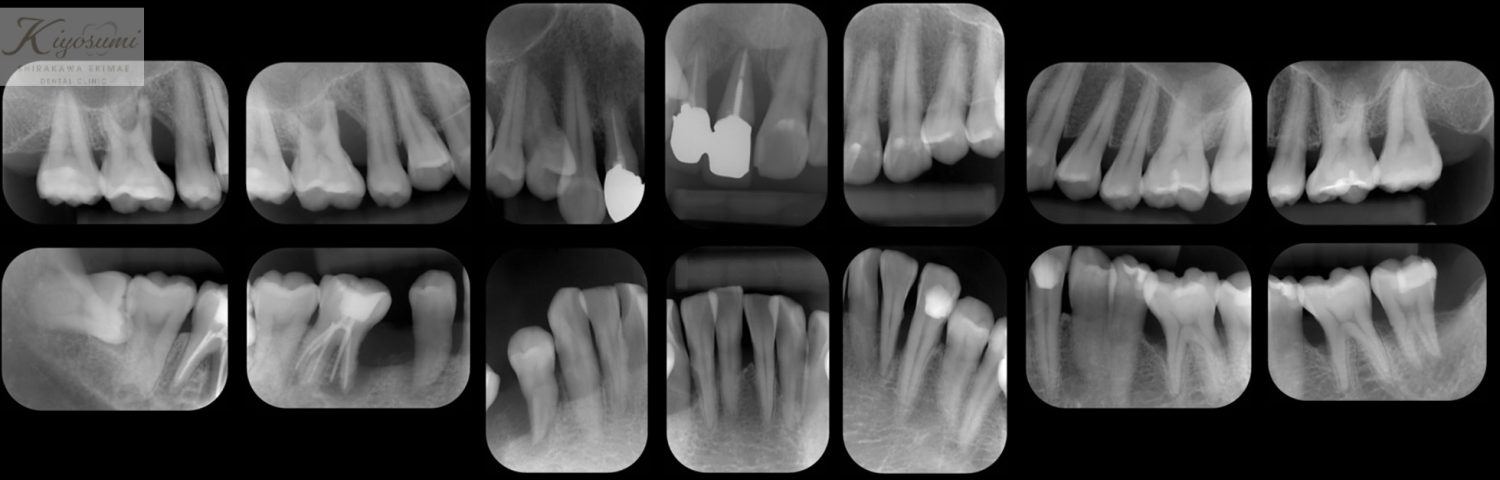

| 主訴 | 歯が揺れて噛めないので、噛めるようにして欲しい。 |

| 治療内容 | 基本的な歯周病治療、根の治療を実施し、歯の高さが足りない箇所は歯冠長延長術、保存が難しい歯は一部歯根分割抜去を行いました。欠損部はインプラントを用いず、ジルコニアブリッジで仕上げています。 |

| 想定されたリスク | ※残存している歯の本数が少ないため、残っている歯だけでブリッジを行うには長期予後が見込めない可能性があり、患者さんにご理解をいただいたうえで被せ物を行っています。 ※歯周病治療や根の治療をしても歯を残せない可能性がありました。 |